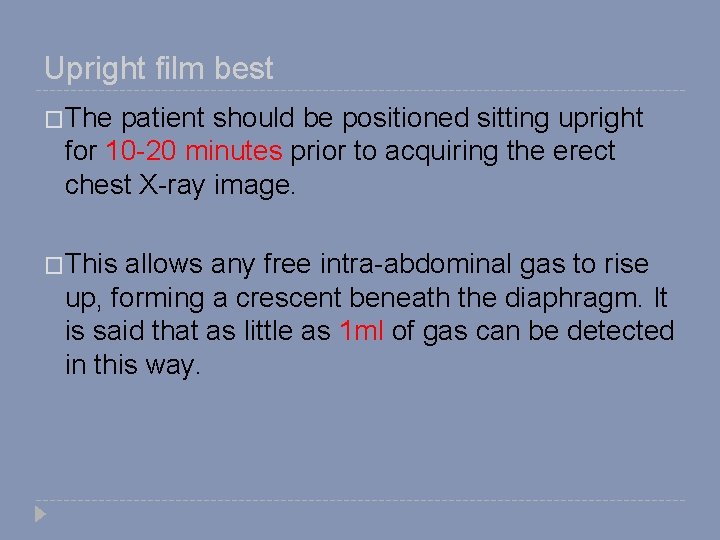

Upright film best �The patient should be positioned sitting upright for 10 -20 minutes prior to acquiring the erect chest X-ray image. �This allows any free intra-abdominal gas to rise up, forming a crescent beneath the diaphragm. It is said that as little as 1 ml of gas can be detected in this way.